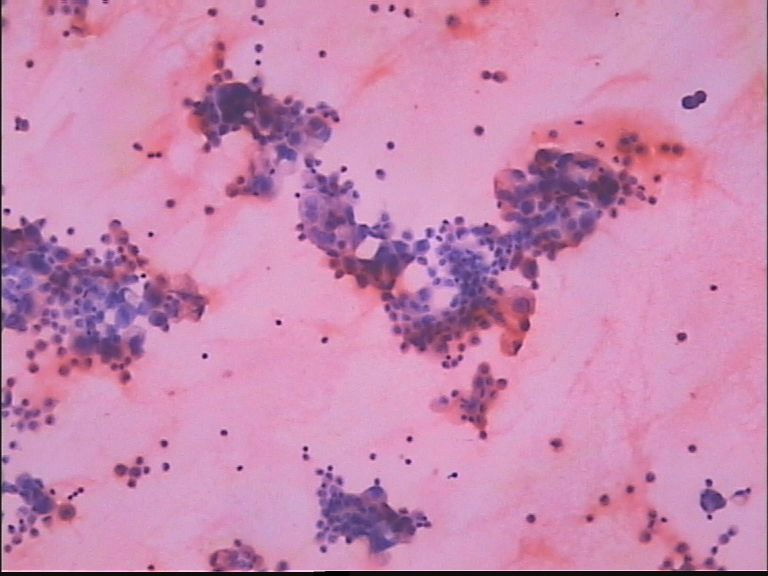

胸水 男67岁

• 胸水 男67岁图1

图1